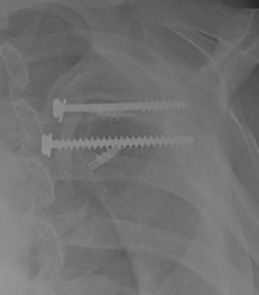

Fixation methods

- screw fixation +/- soft tissue washer

Screw fixation

Screw + soft tissue washer

Medial row anchors and lateral screws for missed lesser tuberosity avulsion in adolescent